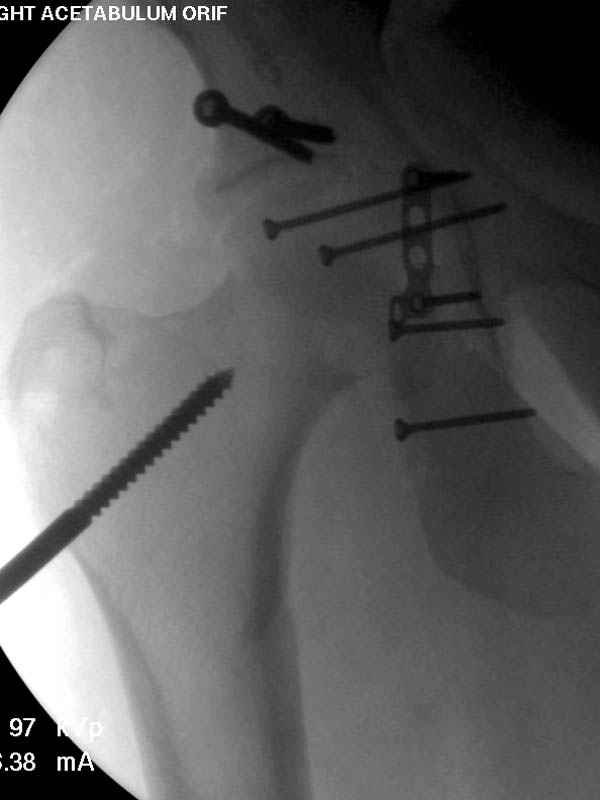

Наш недавний случай перкутанной фиксации "методом

Сиэтла" спицами 2.8 мм с резьбой на конце.

Прооперирован вчера на 13 день после поступления.

Больному 41 и из-за гемодинамической нестабильности в течение первых 7 дней был в реанимации под интубационной седацией.

Кроме перелома плеча у больного старый дистракционный перелом T12-L1 оперированный когда-то и кем-то, открытый перелом костей предплечья, который был прооперирован в ночь поступления, после I&D (хирургической обработки). Из-за разрыва селезенки при поступлении травма хирургами произведено удаление.

Дополнительно имеется перелом ацетабулума: задняя

колонна с полупоперечным переломом, и переломы костей лица.

На седьмой день зафиксирован перелом ацетабулума через задний доступ. Перед операцией для профилактики DVT, IVC фильтер, также получает Lovenox.

После операции на ацетабулум был экстубирован, сегодня опять же интубирован, из-за невменяемости и казуса, проявления "вампирства" - опустошил посуду с кровью от дренажа.

Извиняюсь за качества снимков, обычный больной в 300 фунтов, портативным ренген аппаратом не пробить.

Djoldas Kuldjanov, MD

Department of Orthopedic Surgery

St. Louis University Medical Center